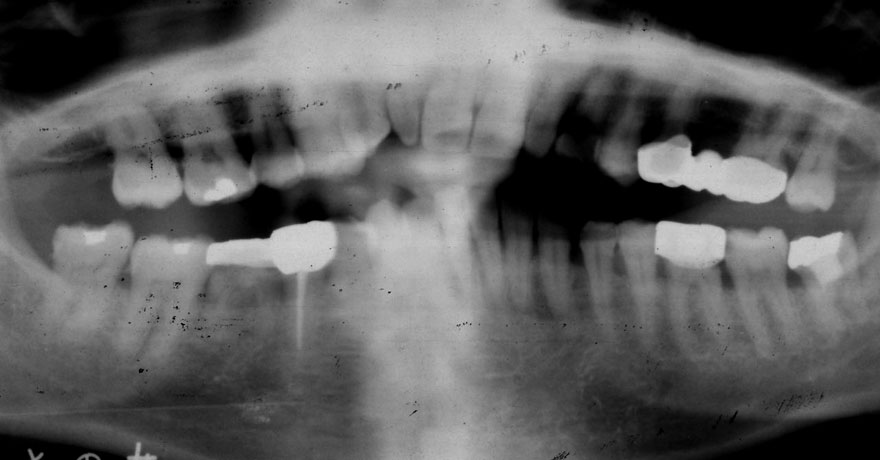

初診時 52歳 女性 平均歯槽骨喪失量:4.75mm

河田歯科医院

24年後 74歳

平均歯槽骨喪失量:6.13mm

21年間喪失量:-1.38mm

年間喪失速度:-0.057mm

(ケア頻度:1.25ヵ月ごと)